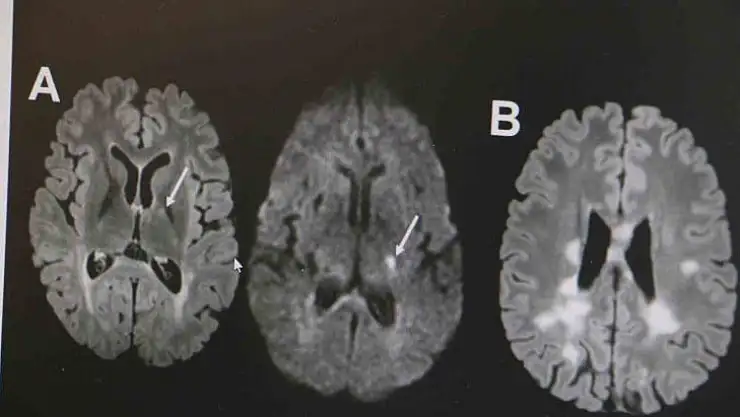

MS hastalığının kadın popülasyonunda daha sık görüldüğünün altını çizen Demir, "Kadınlarda erkeklere göre bu hastalık yaklaşık 2 kat daha sık görülmekte. MS hastalığı özellikle ataklarla seyreden bir hastalıktır. Hastaların yüzde 85’inde relapsing remitting form dediğimiz atak formuyla seyretmektedir. MS hastalığının tanısı klinik olarak kesin tanı konulabilse de günümüz şartlarında MR çekilmeden kesin tanı konulmaması önerilmektedir. MS hastalığının tedavisine gelecek olursak, kesin bir tedavisi yoktur. Ancak son 10 yılda çok sayıda ilaç kullanıma girmiştir. Bu açıdan MS hastalığı kontrol edilebilir bir hastalıktır. MS hastalığına bağlı ataklara karşı hastalara steroid tedavisi vermekteyiz. MS hastalarında görülen her şikayet atak olmayabilir. Özellikle idrar yolu enfeksiyonu, üst solunum yolu enfeksiyonu, aşırı egzersiz durumlarında, sıcak bir ortamda bulunma gibi durumda hastalarda ısı artışına bağlı olarak daha önceden var olan semptomlarda kötüleşme olabilir. Bunlar daha çok yalancı atak diyebiliriz. Ancak atak diyebilmemiz için şikayetin en az 24 saat sürmesi gerekmektedir" ifadelerinde bulundu.